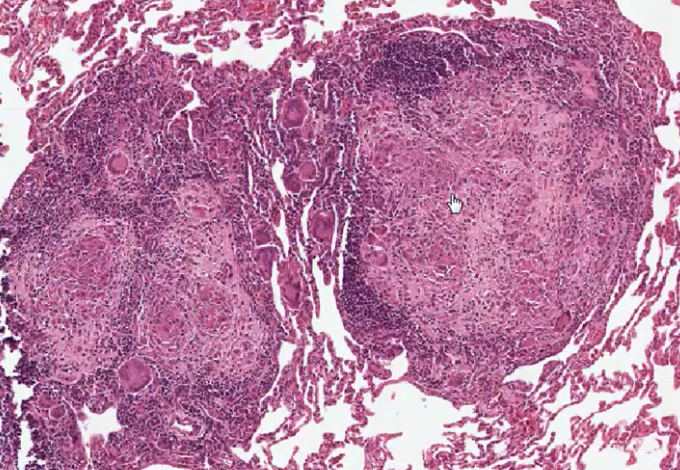

What is this?

Caseating Granuloma